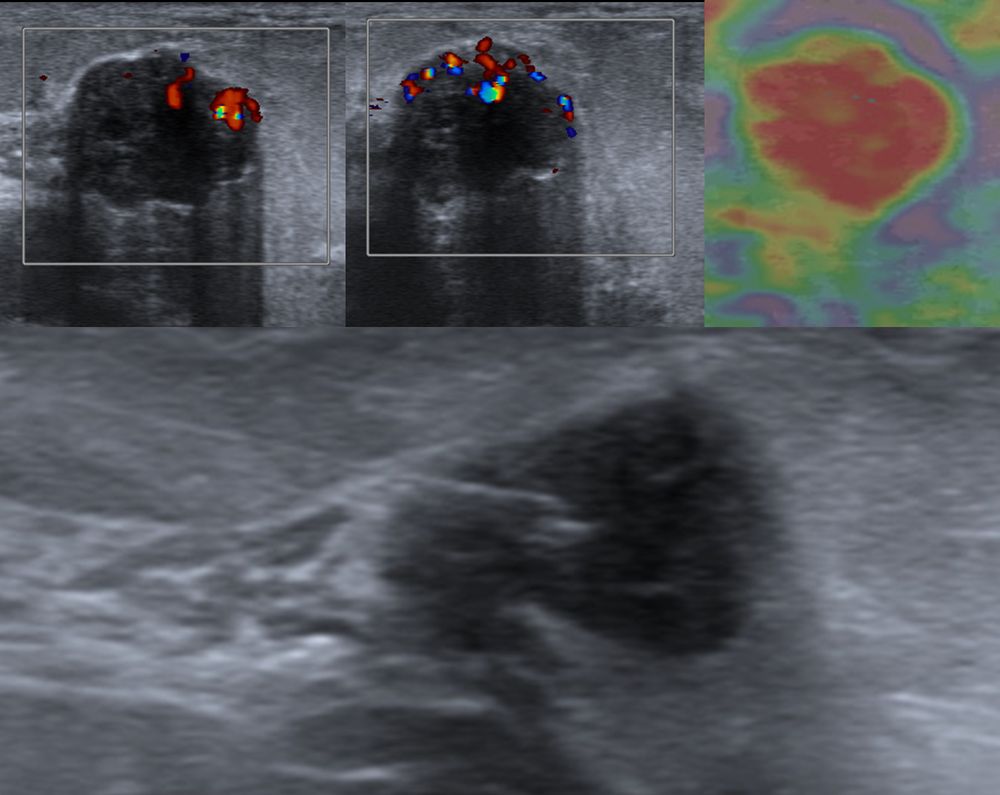

- Παρακέντηση με λεπτή βελόνη - FNA (fine needle aspiration). Είναι η απλούστερη επεμβατική μέθοδος βιοψίας μαστού. Υπό συνεχή υπερηχογραφική καθοδήγηση εισάγεται μια λεπτή βελόνη εντός του ύποπτου ευρήματος και αναρροφάται το περιεχόμενο, το οποίο μπορεί να δοθεί για κυτταρολογικό έλεγχο και/ή καλλιέργεια σε υποψία φλεγμονής.Είναι γρήγορη και είναι πολύ καλά ανεκτή χωρίς επιπλοκές. Η μέθοδος εφαρμόζεται:

- Υπερηχογραφικά καθοδηγούμενη βιοψία μαστού - core biopsy

Εχει αντικαταστήσει την FNA στις συμπαγείς βλάβες του μαστού, γιατί η ποσότητα του ιστού που συλλέγεται είναι μεγαλύτερη και το αποτέλεσμα πιο αξιόπιστο.